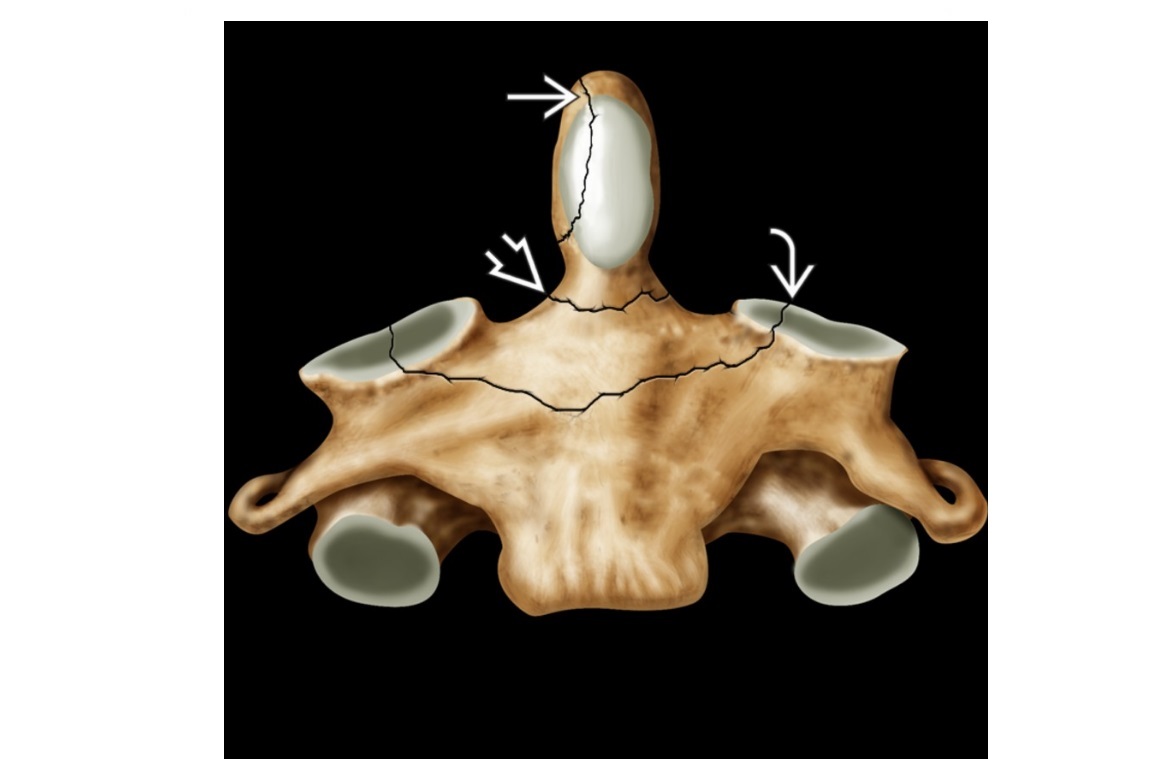

Types of odontoid fracture?

A

Type 1 - upper part (rare but usually stable)

Type 2 - base (unstable and most common)

Type 3 - through the dens and into the body of C2(unstable, but best prognosis for healing)